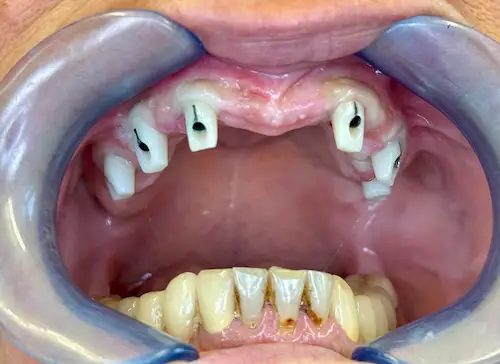

Unser 55-jähriger Patient stellte sich uns nach Jahrzehnten der Nichtbehandlung mit einen stark kariösen und nur zum Teil bezahnten Kiefer vor. Aufgrund einiger abgebrochener Zahnwurzeln wurde schnell ersichtlich: Der bisherige Zahnersatz kann nicht erneuert werden; außerdem wünschte sich unser Patient in Zukunft einen gaumenfreien festsitzenden Zahnersatz. Alles deutete Richtung All-on-4 ® / All-on-6 ®–Konzept.

Patientenbild: Ober- und Unterkiefer vor der OP

Der chirurgische Eingriff im Detail

Der Tag der Operation ist gekommen: Im ersten Schritt werden die noch vorhandenen Zähne gezogen sowie die Wurzeln und vereinzelte Zysten restlos entfernt. Dies erwies sich im vorliegenden Fall als extrem komplex und folgenreich: Beim Extrahieren gingen Teile der Knochenwände verloren, was einen deutlichen Mehraufwand beim Aufbau des Kieferkamms nach sich zog. Zuzüglich zu Knochenersatzmaterial verwendete Dr. Mintert dafür 2 Collagen Blöcke, 2 Membranen und 0,3 ml Emdogain. Letzteres dient der Entwicklung von zahnstützendem Gewebe. Auch Eigenknochen aus einem zweiten OP-Gebiet kam zum Einsatz. Im Oberkiefer wurde außerdem ein sogenannter Sinuslift durchgeführt, der – vereinfacht gesprochen – die Kieferhöhlen anheben soll. Nun waren die Grundlagen für den nächsten Schritt geschaffen: Eine eigens angefertigte Bohrschablone ermöglicht die navigierte Implantation. So fanden alle acht Implantate trotz ungeplanter Komplikationen ihren rechten Platz im Mundraum. Abschließend wird L-PRF Plasma, d.h. zentrifugiertes Eigenblut eingebracht, um die Wundheilung zu unterstützen. Als Zahnersatz werden zwei festsitzende Keramikbrücken gewählt und auf künstliche Keramikaufbauten geklebt. Diese wiederum sind mit jeweils vier Implantaten verschraubt.